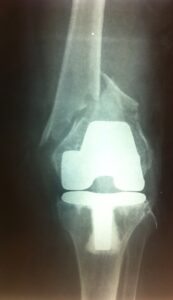

- Περιπροθετικό κάταγμα στην περιοχή του γόνατος , πολύ περιφερικό.

- Η ίδια ασθενής σε profile ακτινογραφία.

- H οστεοσύνθεση με ανάστροφη ενδομυελική ήλωση με πολύ μικρή τομή δέρματος.